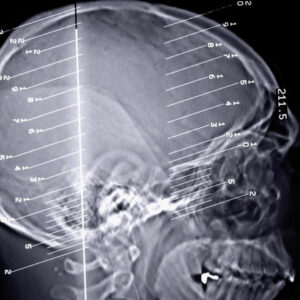

The human body can perform all its functions seamlessly when every organ of the body works in unison to perform the task. A slight change in the functions of the organ can disrupt the entire functioning of the body. Epilepsy seizures are a kind of disorder that occurs when we there is a problem in our brain’s electrical system.